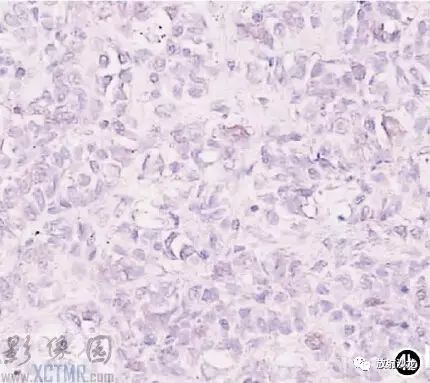

手術所見:腫塊位于食管,約15cm*6cm,上界到喉甲狀軟骨氣管起始處,下達胸骨后,質軟,與食管粘連緊密,周圍無明顯侵犯,無法完全切除,行活檢送病理檢查。病理:送檢組織切面呈魚肉狀;鏡下見腫瘤細胞彌漫排列,核大,深染,多圓形或不規則,部分核碎裂,胞漿淺淡,多少不等;免疫組化:S 100(-),HMB45(-),CK(-),CD3(-),CD20(+),CD45RO(-),CD79a(+),CD21散在(+),Mum-1(+),Bcl-2(-),Bcl-6(-)。診斷:(食管)非霍奇金B細胞淋巴瘤(圖4)。